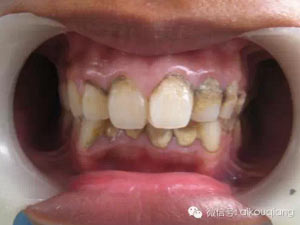

一個(gè)高職學(xué)校的學(xué)生,口腔內(nèi)嚴(yán)重的牙結(jié)石,可能小時(shí)候沒有刷過牙

7.jpg

洗牙(潔治)后效果很明顯